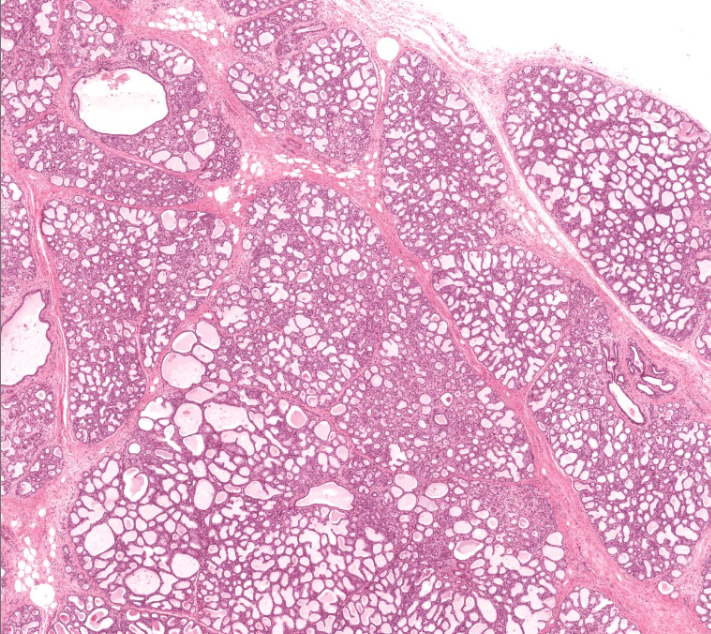

pancreas

looks like a shitty purple unicorn horn

exocrine secretes digestive enzymes

endocrine releases insulin and glucagon

lobe (red) and lobule (blue) of the pancreas

type of cell

exocrine cells of the pancreas

secrete insulin and glucagon

shaped like a slice of pie

structure

islet of Langerhans of the pancreas

endocrine cell

secrete hormones for digestion

parotid gland

you can tell bc of the of the white holes

secretes mucus and watery fluid